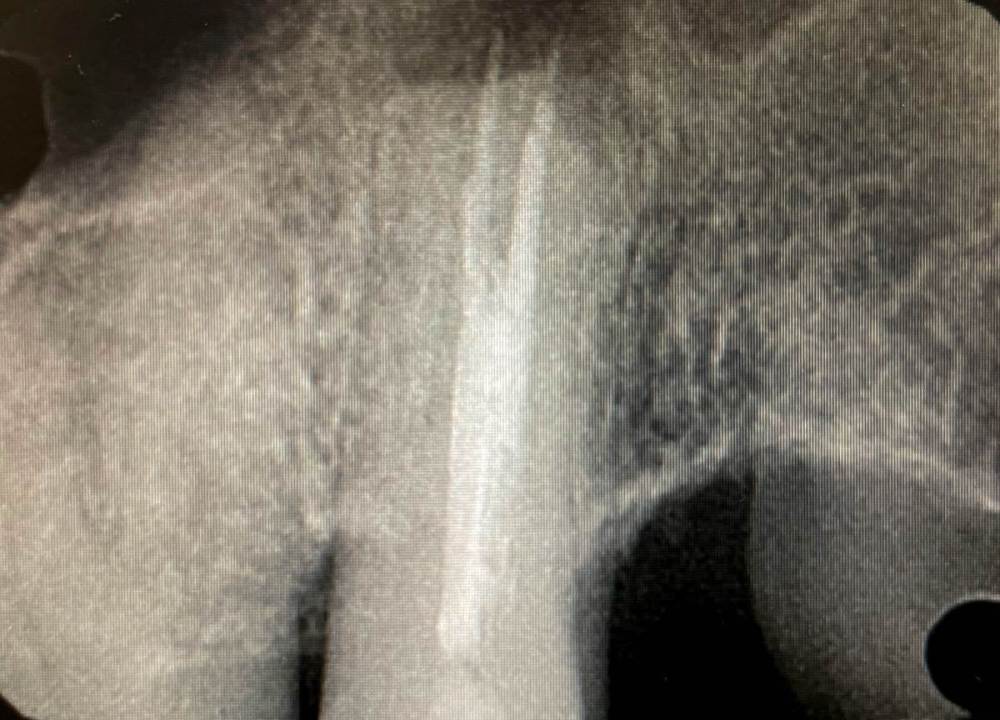

Кирилл Якимов Опубликовано 5 мая, 2022 Поделиться Опубликовано 5 мая, 2022 Добрый день, дорогие коллеги! Я начинающий врач, очень нужна конструктивная критика) 2.7 зуб, каналы лечили несколько лет назад(пациентка точно не помнит). Зуб не беспокоит. Сделал прицельные снимки + КТ. Есть очаг перирадикулярной деструкции+гуттаперча за апексом+резорбция. Принял решение зуб перелечить. Убрал старую пломбу и кариес, гутта в каналах мягкая, распломбировал довольно быстро Profile 25.06 25.04 и желтый Mtwo со стеночек+активация гипохлорита 3% U-file 15 стальным. Из-за апекса гуттаперчу вытащил H-file. В первый визит расширил до 70 K-file. Длина обеих каналов 18мм. Оставил кальций на 2 недели. Коллега микроскопист говорит, что нужно делать пробку МТА, дальше обтурация гибридной методикой, затем коронка и контрольное КТ через 6 мес. Подскажите пожалуйста, как и чем все таки лучше пломбировать такой зуб и какой наиболее вероятный прогноз? Кто что думает, в чем может быть причина такой резорбции? Ссылка на комментарий